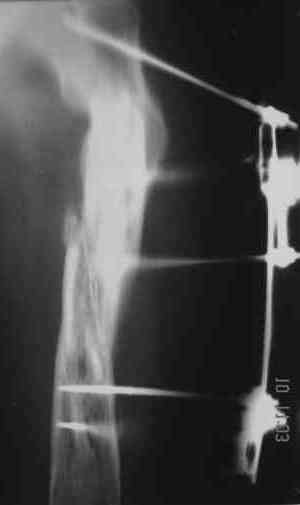

Уважаемые коллеги! Пришел на консультацию вот такой больной (первые 3-и рисунка). Травма автодорожная, апрель 2006г. Лечился консервативно, вытяжение и гипс. Через пять месяцев стал ходить. Укорочение бедра 6 см. 26 февраля 2007г. оступился, упал. Прооперирован в г.Баку - наложен стержневой аппарат. Ходит с костылями, наступая на левую ногу. Мы попросили что нибудь из ранних снимков. Принес рентгенограммы перелома (рис. 4,5). Посмотрели, наснимали сами (рис. 6-10). Похоже, что нет сращения нигде. Хотелось - бы обсудить следующие вопросы:1. дальнейшая тактика - реостеосинтез или подождать (ослабить аппарат, дать нагрузку и т.д.)?2. если реостеосинтез - то чем и как? Юрий Алексеевич Булахтин